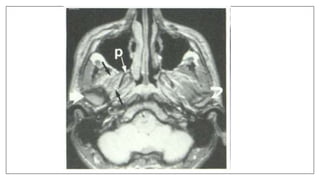

Motion artifacts: Phase-encoded Motion Artifacts

Bright noise or repeating densities in the phase

direction, as the results of motion during acquisition of a

sequence.

 arterial pulsations, swallowing, breathing, peristalsis,

and physical movement of a patient.

Moving Coil

Two examples where the patient moved while attached to the posterior neck

coil, moving the coil.

Patient Leaving Magnet

In this case the patient pushed the head coil out of position in the middle of the

scanning sequence. patient was in a hurry to leave!

Uncontrolled Coughing

The patient had a fit of uncontrolled coughing during this axial T1-weighted

lumbar spine scan.

Swallowing Motion

Patient motion during a scan will cause artifacts to propagate in the phase

direction. The image on the left demonstrates the artifact generated by the

patient swallowing. Area of increased signal intensity in the spinal cord.

REMEDY :

Applying pre saturation RF pulses to the anatomy that was generating the

artifact.